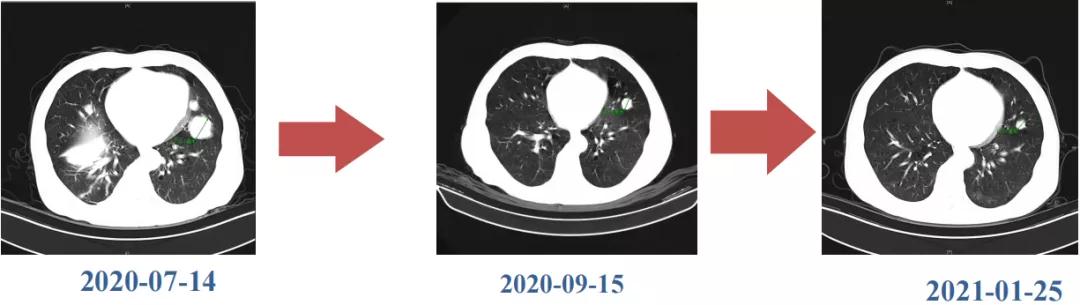

肝脏弹性超声:12kPa。腹部MRI平扫+增强:肝巨块结节性HCC(最大径18.4cm)伴肝内多发转移(最大径3.5cm),肝右静脉广泛癌栓形成;肝硬化伴门脉高压、脾大、少量腹水;肝囊肿;双肺多发转移。胸部CT平扫:两肺多发转移,两肺气肿伴肺大泡,两肺散在慢性炎症,右侧少量胸水。

Δ肺CT:双肺多发转移

肿瘤学评估(用药后2个月对比6个月):肝内主瘤明显缩小,动脉期强化降低;子灶消失;门脉右支癌栓明显缩小坏死;肺转移灶缩小,大部分消失。

Δ治疗过程中病灶影像学变化